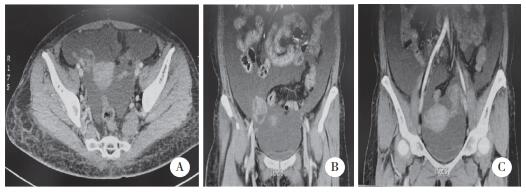

患者入院时一般状态欠佳,心率达120次/min,血压84/62 mmHg,体温36.6 ℃,呼吸16次/min。妇科查体:双附件区厚,子宫直肠窝空虚。完善实验室检查。血清肿瘤标志物:CA125 789 U/mL,HE4 156.3 pmol/L,其余肿瘤标志物未见异常。盆腔超声提示:右侧卵巢大小约4.2 cm×2.4 cm,形态欠规整,回声不均匀(图 1A),内见数个囊泡样回声,大者直径约0.92 cm,其内清晰(图 1B);右侧卵巢内还可见低回声,大小约1.8 cm×1.6 cm,未见血流(图 1C);左侧卵巢大小约2.5 cm×1.6 cm(图 1D)。全腹增强CT提示:双侧附件区生理性囊肿可能大(图 2)。炎症相关指标:C反应蛋白12.6 mg/L。其余检查发现,患者合并肺栓塞、下腔静脉和左肾静脉血栓不除外,胸腔积液,心包少量积液,低氧血症,低蛋白血症,离子紊乱(低钾、低钠、低钙),肾功能不全。给予患者吸氧、纠正离子紊乱、消炎、抗凝等一系列对症支持治疗。患者入院第2天腹泻加重,呈水样便,每日高达10余次,给予止泻治疗。患者因呼吸困难、腹胀难忍,遂行腹腔穿刺放腹水,标本送检未发现瘤细胞(图 3)。因患者目前存在多脏器损害和多浆膜腔积液等症状和体征,且我院的影像学检查和腹水化验均无法得到卵巢恶性肿瘤的诊断,故请风湿免疫科医生会诊,建议行风湿免疫相关生化检查。结果回报:抗核抗(+),1∶320,核颗粒型;抗SSA抗体(3+),抗SSB抗体(3+);抗Ro-52抗体(2+);单项补体C3 0.23 g/L,单项补体C4 0.01 g/L,红细胞沉降率66 mm/h。风湿免疫科会诊结果:除外妇科肿瘤和感染后,考虑SLE可能性大,建议转入风湿免疫科进一步诊治。患者和家属拒绝进一步诊治,患者于2020年11月5日因急性肺栓塞、呼吸衰竭死亡。

| A,右侧卵巢形态欠规整,回声不均匀;B,右侧卵巢内见数个囊泡样回声,其内清晰;C,右侧卵巢内低回声,未见血流;D,左侧卵巢. 图 1 盆腔超声图像 |